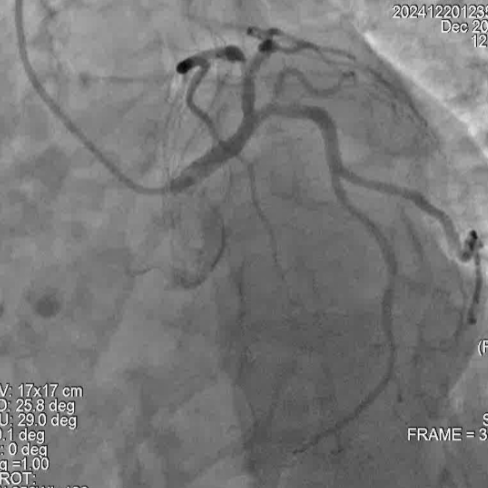

冠脉造影

手术过程

尹秋林主任表示本次手术很顺利。该患者左冠和右冠病变均较为局限,且患者及家属对植入生物可吸收支架意向强烈。在腔内影像IVUS的引导下评估管腔尺寸,病变性质后做精准预处理。本次手术中FIRESORB®具有较好的推送性,径向支撑表现也很好。我们会持续关注患者术后的恢复情况。